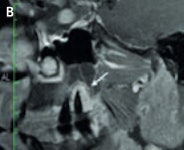

An example of cone-beam CT. In this instance, the lower left third molar (d. 38) was imaged after panoramic radiograph with CBCT. The arrows mark the mandibular canal. Images courtesy of Dr. Anni Suomalainen.